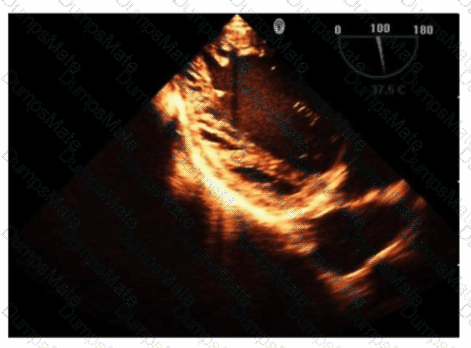

Which finding is shown in this image?

AE-Adult-Echocardiography Question 4

Options:

A.

Chiari network

B.

Left atrial thrombus

C.

Cor triatriatum

D.

Artifact